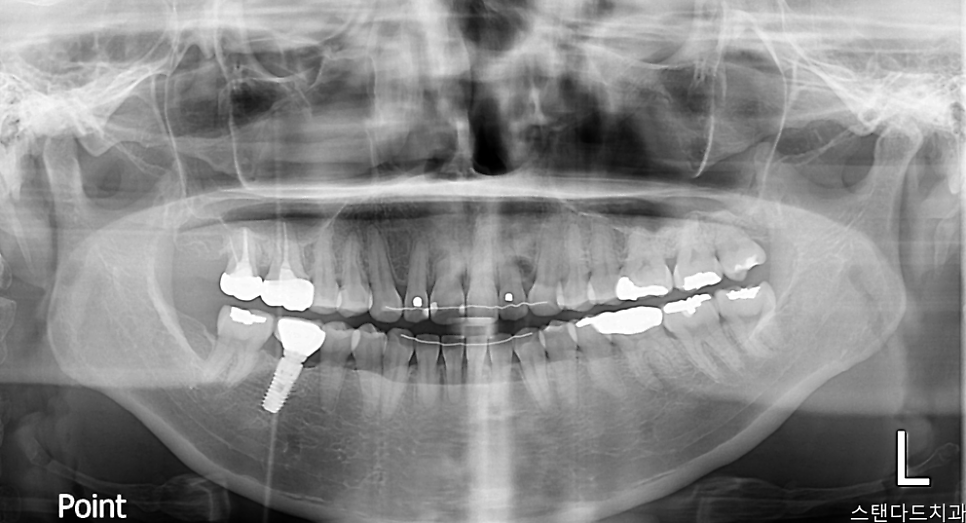

치료 전 상태

• 중앙 앞니(중절치) 사이 공간이 벌어져 있어 심미적으로 위축된 상태

• 치아 표면에 불규칙한 착색이 광범위하게 진행됨

• 치아 끝단 라인이 매끄럽지 못해 거친 느낌